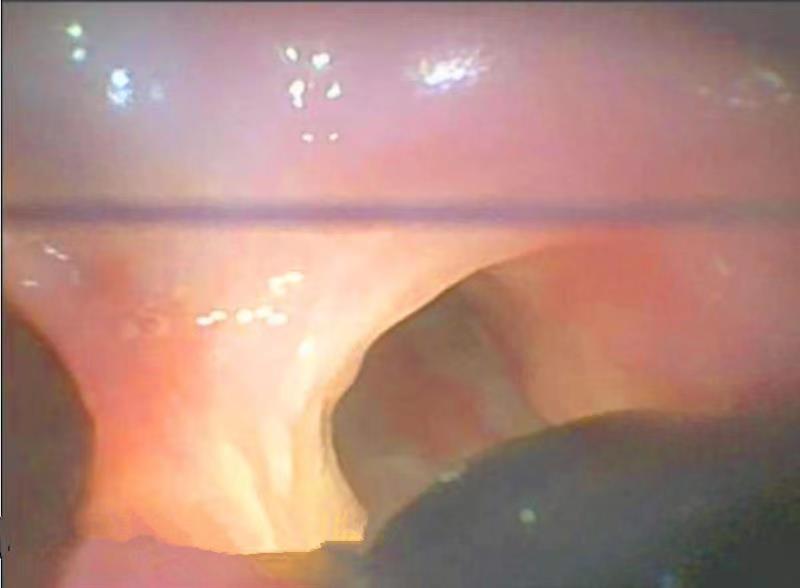

果然,当靖秋生将气管镜向下推行到左右支气管交叉口,即隆突处时,他通过气管镜探头传回的画面看到了刘敏操作的胃镜。之所以能够看到,就是因为患者气管在隆突处破了一个1厘米大小的洞,且这个洞向后方延伸又深入到了食管,通过它的“桥连”,食管和气管在这里异常互通了。这就是张师傅一吃饭就咳嗽,一咳嗽就喷饭粒的原因。

图二、呼吸内镜行至隆突处(左右支气管分叉处)时遇上了胃镜(右下角黑色处)。